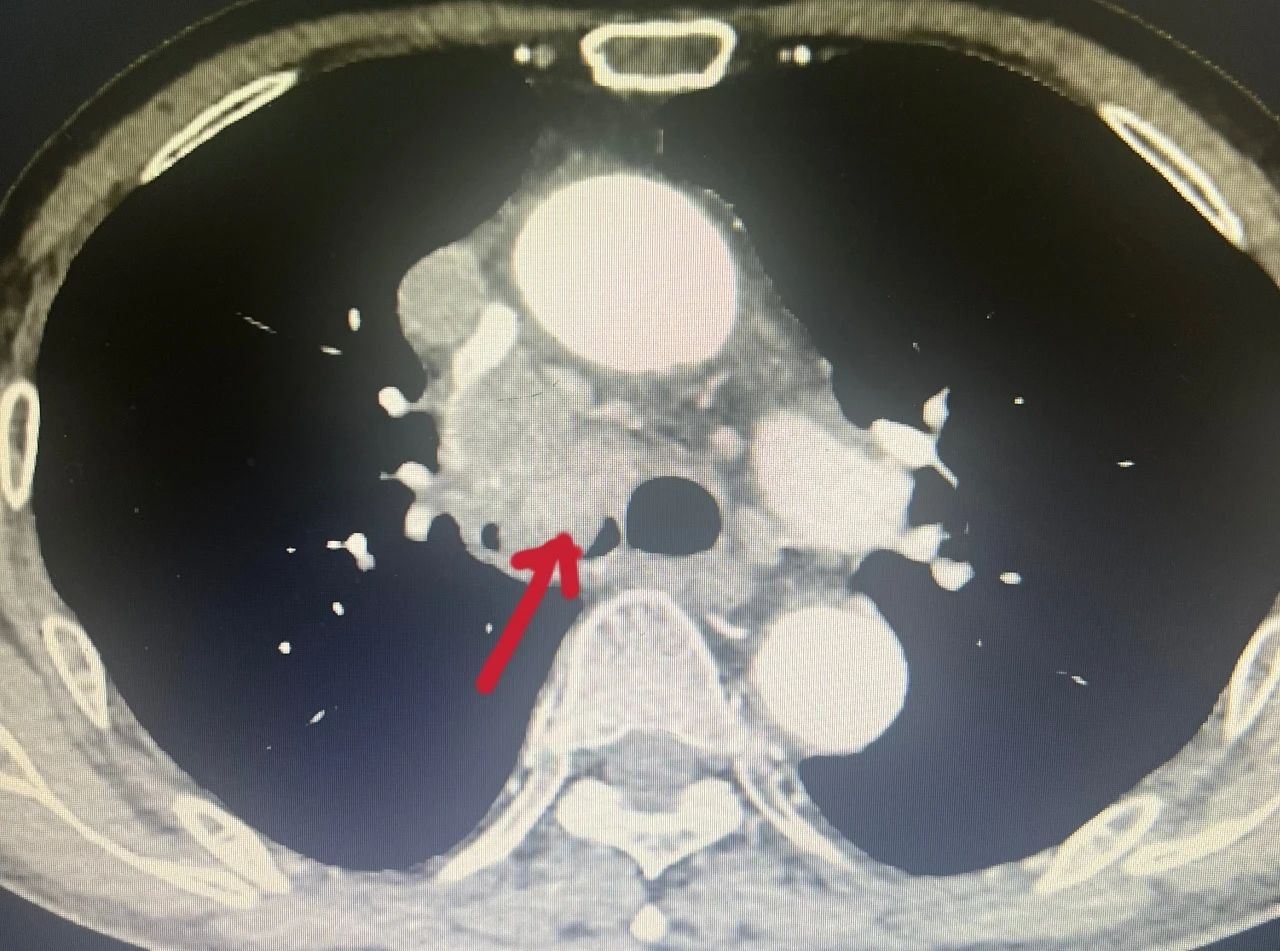

当前位置 :网站首页 > 医院文化 “支气管肿瘤”对人们来说比较陌生,它是呼吸系统的少见病症,以往的常规治疗手段是手术切除肿瘤后进行气管重建,手术难度大、风险高。为了减轻支气管肿瘤患者的身体负担,景德镇市第一人民医院呼吸与危重症医学科积极推动技术创新,成功引进并成熟开展多例经支气管镜高频电圈套切除术,为多名支气管肿瘤患者顺利“拆弹”,使患者们恢复畅快呼吸。 CT显示右侧气管内有巨大肿瘤 李大爷今年71岁,六个月前确诊为肺肉瘤样癌,一个月前间断性咳血,呼吸困难,最近感觉情况加重,到景德镇市第一人民医院呼吸与危重症医学科就诊。11月30日,患者出现意识模糊、血气提示急性呼吸衰竭。 “呼吸的通道堵塞严重,情况很危险,随时都可能窒息。”市一院呼吸与危重症医学科主任卢志军介绍。通过综合评估患者年龄、耐受能力、影像学特征,呼吸与危重症医学科团队最终决定对患者实施支气管镜高频电圈套器肿瘤切除术。“这样可以切除病灶,迅速解除气道阻塞,缓解症状”。 卢志军正在进行支气管镜手术(资料图片) 术前工作准备就绪,手术紧张有序的进行。随着气管镜进入患者的主气管时,看到患者右侧主气管内一个圆形“硕大”的肿瘤,卢志军通过电圈套器对肿瘤进行套扎,同时使用氩气刀辅助切割和止血,肿瘤顺利切除,随后采取冷冻处理减少肉芽和肿瘤组织生长,最后使用电凝术对肿瘤根部进行最后的处理和止血,手术用时仅15分钟,最终气道顺利再通,末梢血氧也由术前的60%升至正常。李大爷现已顺利出院。 术前术后对比图 经支气管镜高频电圈套切除术是呼吸内镜下支气管肿物切除术常用手段之一,通过纤支镜检查可以在镜下直视气管、支气管的粘膜是否发生病变、管腔是否通畅,通过对病变部位进行组织活检、刷检以及肺泡灌洗可协助疾病诊断。此外,通过支气管镜还可以进行较多的镜下治疗,高频电圈套就是其中一种。该项技术利用高频电圈套将气管内的新生物套住,自新生物根部将其切除,高频电圈套的优点是可以切除较大块的肿物,并且出血少、安全性高、患者花费低、操作时间短,甚至仅使用局部麻醉就可以完成,与全身麻醉相比,并发症少,安全性更高。对于气管、支气管的气管息肉、良性肿瘤、平滑肌瘤及恶性肿瘤的姑息治疗,有较好的治疗效果。 呼吸与危重症医学科简介 景德镇市第一人民医院呼吸与危重症医学科成立于2010年10月,经过不断发展壮大,现已形成具有规模和专科医疗特色的医教研全面发展的科室,2020年与江西省胸科医院为省市共建学科。 科室开放普通床位 98 张,重症监护床位 6 张。配有医师 19人,护士 64人,其中医师高级职称 6人,主治医师 9人,住院医师 4 人,副主任护士4人,主管护师 4人等,其中硕士 5 人。 除了呼吸科常见病、慢性阻塞性肺病、各种呼吸衰竭及间质性肺病、肺结节病及肺心病等呼吸危重症疾病的诊治,近年来,科室不断开展了肺癌的早期诊断及个性化治疗,支气管镜检查、内科胸腔镜检查及各种介入治疗,及置入细管胸腔闭式引流术治疗气胸及胸腔积液, 经彩超或 CT 引导经皮肺穿刺活检技术,经支气管镜肺活检,肺段灌洗,钳取异物,经支气管镜引导气管插管术,经支气管镜氩气刀治疗技术、冷冻治疗技术,球囊扩张,支架植入治疗恶性肿瘤大气道狭窄,内科胸腔镜诊疗技术,经皮穿刺置入 125I 粒子治疗肺恶性肿瘤技术,床旁支气管镜检查等各种急危重症救治技术等。还有已购入超声支气管镜和硬质支气管镜,即将开展超声支气管镜检查及淋巴结穿刺活检术,硬质支气管镜技术等。